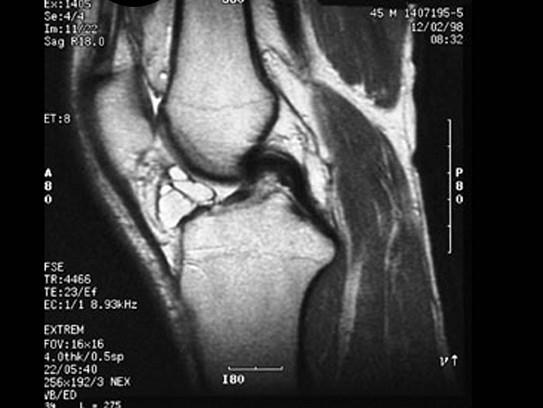

问题 男,45岁,右膝关节曾有外伤史,右膝关节活动后感不适数月,请结合所提供的图像,选择最佳选项 ( )

选项 A、半月板损伤 B、后十字韧带撕裂 C、前十字韧带撕裂 D、前十字韧带腱鞘囊肿 E、未见异常

答案 D